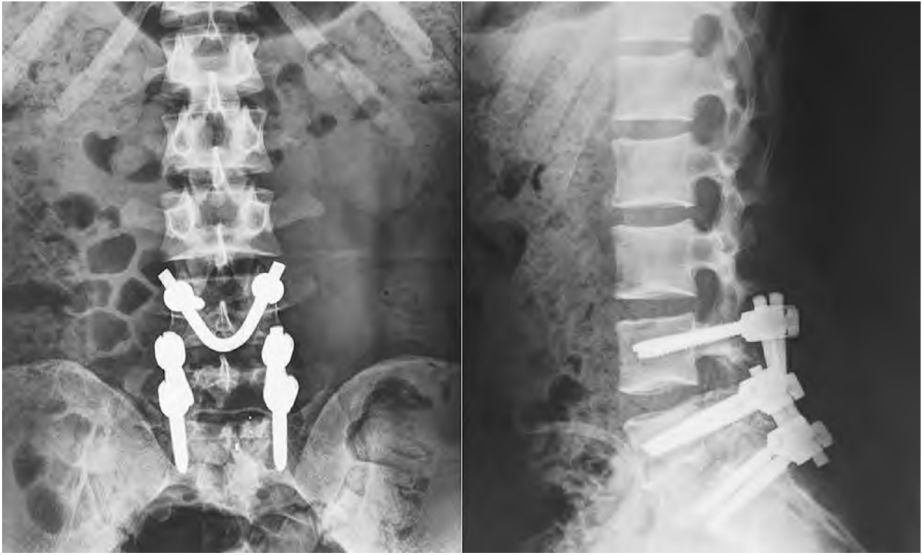

椎弓根螺釘聯(lián)合“V”型棒內(nèi)固定技術(shù)

該技術(shù)于病變椎體雙側(cè)置入萬向椎弓根釘,清理峽部斷端并植骨,將預(yù)彎的V形棒穿過棘突間隙后,將棒兩端分別穿過兩側(cè)萬向椎弓根釘尾部,將棘突向頭側(cè)適當(dāng)推壓提拉,加壓峽部斷端后鎖緊椎弓根釘螺帽。

L4/L5椎弓根釘聯(lián)合V形棒內(nèi)固定;

L5/S1椎弓根螺釘內(nèi)固定

有文獻(xiàn)顯示,椎弓根釘聯(lián)合“V”形棒內(nèi)固定技術(shù)的優(yōu)勢(shì)在于:

①內(nèi)固定物不經(jīng)過峽部,植骨區(qū)不會(huì)受內(nèi)固定物的影響,而且骨融合后內(nèi)置物不必常規(guī)取出;

②手術(shù)方法簡(jiǎn)單、學(xué)習(xí)曲線短;

③能在下腰椎后結(jié)構(gòu)形成張力帶作用,使峽部盡早骨愈合;

④椎弓根釘聯(lián)合 V 形棒內(nèi)固定提供的穩(wěn)定性可在術(shù)后早期明顯緩解患者的腰痛,明顯減輕相應(yīng)節(jié)段椎間盤壓力,緩解椎間盤退行性改變。